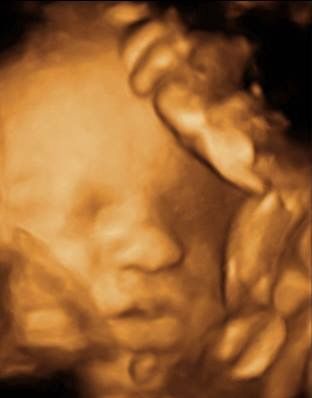

Ecografia 3 D e 4D. Alcuni ecografi, grazie a particolari sonde, hanno la possibilità di effettuare ecografie tridimensionali (3D) e quadridimensionali (4D). Queste ecografie, oltre a trovare sempre più impiego in ginecologia ed ostetricia per facilitare la diagnosi di varie patologie (spina bifida, alcune patologie del sistema nervoso e cardiache fetali, malformazioni uterine, etc.), vengono da anni utilizzate per far conoscere ai futuri genitori loro figlio. La visualizzazione del feto in 3D e 4D consente di iniziare già durante la gravidanza il rapporto affettivo e relazionale con il proprio bambino. Le immagini tridimensionali sono ferme ed è possibile vedere il feto da varie prospettive, mentre l’ecografia 4D da la possibilità di osservare le immagini tridimensionali in movimento. Per ottenere delle buone immagini è necessario che il feto sia posizionato adeguatamente, che ci sia una buona quantità di liquido amniotico e che la futura mamma non pesi troppo (il tessuto adiposo non lascia passare gli ultrasuoni adeguatamente).

Ecografia 3D e 4 D imageEcografia 3D e 4 D imageEcografia 3D e 4 D image